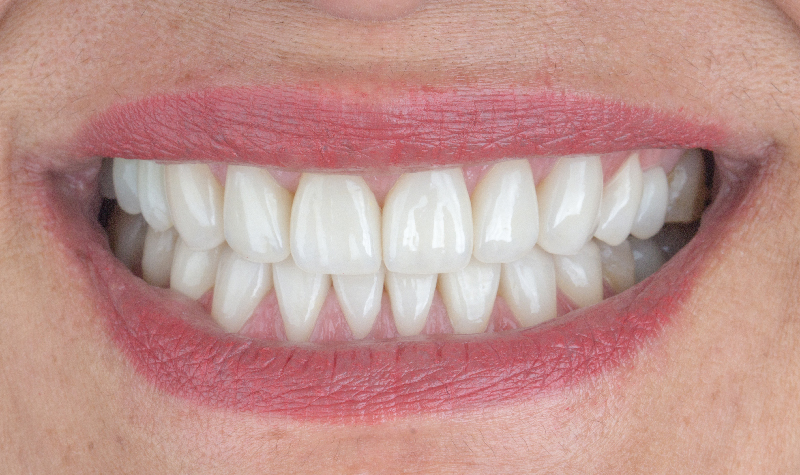

Diseño de Sonrisa Digital con carillas de cerámicas.